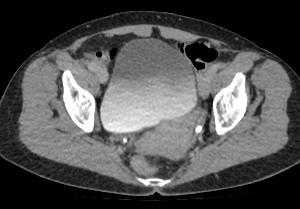

Мультиспиральная КТ мочевого пузыря является частью протокола обследования органов малого таза. Это высокоинформативный рентгенологический метод исследования, позволяющий детально визуализировать мочевой пузырь, нижнюю часть мочеточников, внутренние половые органы, прямую кишку.

Зачастую подобное исследование проводится при мочекаменной болезни (МКБ) для выявления конкрементов, определения их положения, размеров и плотности. Локализация конкремента существенно влияет на терапевтическое лечение МКБ, а наличие дивертикулов стенки мочевого пузыря на возможность самостоятельного выхода камня.

Также при данном исследовании возможно выявить утолщение стенки мочевого пузыря, что при диффузных изменениях может соответствовать проявлениям цистита, а локальные или неравномерные утолщения – характеризовать патологический процесс обусловленный новообразованиями.

Для улучшения визуализации патологических образований, в частности, при подозрении на опухолевый процесс, проводится внутривенное болюсное контрастирование. Методика контрастного усиления основана на введении в вену контрастного препарата, который в большей степени накапливается в патологически измененных участках и обеспечивает их яркую визуализацию на фоне здоровых тканей. Контрастирование дает возможность определить врачу границы опухоли, оценить степень прорастания в соседние органы и ткани, выявить опухоли минимальных размеров (как первичного, так и метастатического характера).

Мультиспиральная КТ используется для диагностики аномалий развития мочевого пузыря, травматических повреждений, воспалительных заболеваний и опухолевых процессов органов малого таза. Преимуществами данного исследования является высокая скорость сканирования и доступная цена. Однако в ряде случаев может быть более предпочтительно выполнение магнитно-резонансной томографии, которая обладает высокой чувствительностью и информативностью для обследования органов и мягких тканей малого таза. В клинике «Доступная медицина» обследование мочевого пузыря входит в протокол МРТ малого таза и его можно пройти на нашем современном оборудовании экспертного уровня